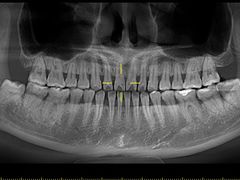

• Dr.Z dental仁康种植矫正中心

• -Dr.Z dental仁康种植矫正中心

毛豆达人 | 20-11-15

报错